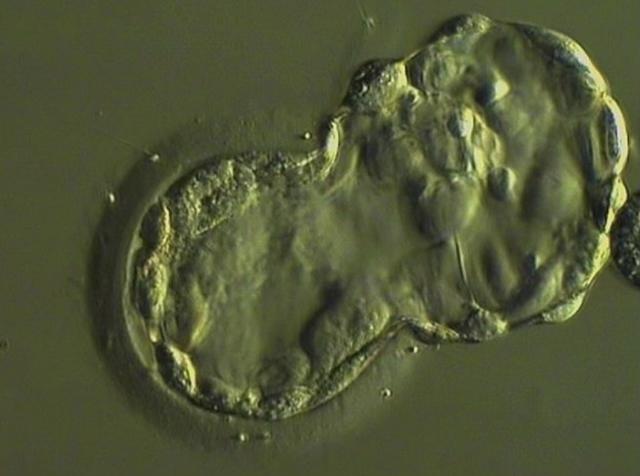

Hi everyone please meet what we’re fighting for, this is our miracle embryo that one day we want to call our little boy or girl 😊❤️